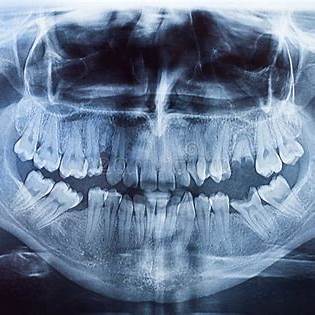

The medical assistant led me to an operating room, then sat me in front of a big-screen television with a giant skeletal image of my mouth. In the upper right, it read: “Rory Hughes: 46 years and 107 days old.”

Underneath, two alerts highlighted in red:

Family history of cancer.

Family history of mental problems.

I’d been reduced to no more than a vessel of generational maladies.